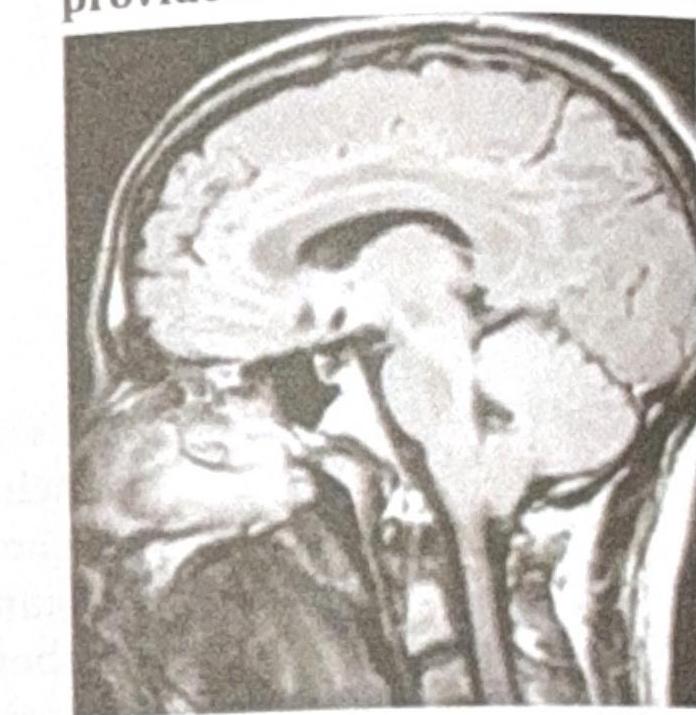

Identify the diagnosis using the MRI provided.

Explanation: ***Chiari type 1 malformation*** - The sagittal MRI image clearly shows the **cerebellar tonsils prolapsing below the foramen magnum** into the cervical spinal canal, which is the hallmark of a Chiari type 1 malformation. - This condition can lead to symptoms like headaches, neck pain, and neurological deficits due to compression of the brainstem and spinal cord. *Dandy-Walker malformation* - This malformation involves the **agenesis or hypoplasia of the cerebellar vermis** and persistent cystic dilation of the fourth ventricle, creating a large posterior fossa cyst. - The image does not show an enlarged posterior fossa with a cystic fourth ventricle or a severely hypoplastic vermis. *Vein of Galen malformation* - This is a **rare congenital vascular malformation** involving a direct arteriovenous shunt without an intervening capillary bed, typically presenting as an enlarged vein of Galen. - The provided image is a sagittal view demonstrating cerebellar tonsillar herniation, not a prominent or malformed vein of Galen. *Agenesis of the corpus callosum* - This condition is characterized by the **partial or complete absence of the corpus callosum**, the band of white matter connecting the two cerebral hemispheres. - On sagittal MRI, this would show absence of the corpus callosum and typically radial gyral patterns, which are not seen in this image.